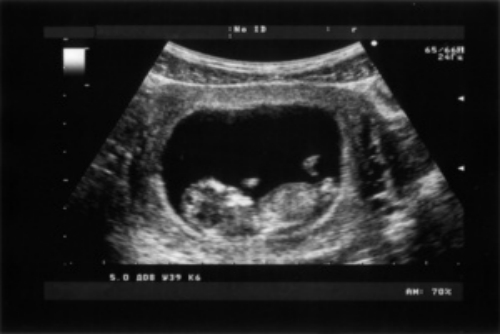

孕期超聲檢查單要怎么看—平創(chuàng)醫(yī)療

孕期超聲檢查,是為了檢查胎兒在子宮內(nèi)的發(fā)育情況,包括胎兒的頭部、四肢、各個臟器、神經(jīng)系統(tǒng)、消化系統(tǒng)、泌尿系統(tǒng)等。孕期超聲檢查單會有胎心監(jiān)護、胎兒的附屬物、胎盤、羊水等項目,一般是看三維彩超、四維彩超、胎兒的臍帶和胎盤情況。

超聲檢測1

孕期超聲檢查能夠及時了解胎兒在子宮內(nèi)的發(fā)育情況,是孕期較為重要的檢查項目。在孕期除了要定期產(chǎn)檢以外,還需要增加對身體的營養(yǎng)補充,有利于胎兒的生長發(fā)育。